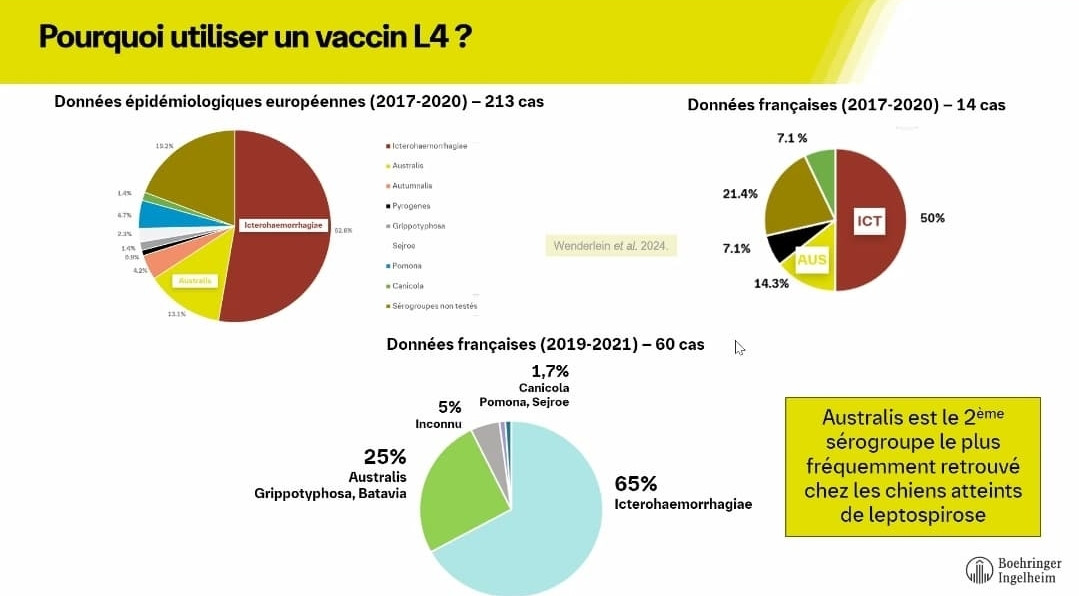

La Leptospirose Canine : Pourquoi la Vaccination est Essentielle

La Leptospirose Canine : Pourquoi la Vaccination est Essentielle

La Leptospirose Canine : Pourquoi la Vaccination est Essentielle

Les Symptômes de la Leptospirose

La Leptospirose Canine : Pourquoi la Vaccination est Essentielle

La Leptospirose Canine : Pourquoi la Vaccination est Essentielle

Les Symptômes de la Leptospirose